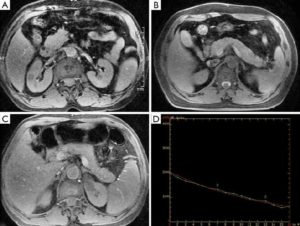

Іншими словами, МРТ можливо як при наявності вже підтвердженого діагнозу для уточнення поточного стану органу, так і в якості діагностичної заходи, коли діагноз ще не встановлений. У всіх цих випадках слід виконати МРТ підшлункової залози – з контрастом або без такого, як порекомендує лікар. Відзначимо, що в обох випадках точність дослідження досить висока, проте контраст дозволяє побачити новоутворення розміром менше двох міліметрів, в той час як обстеження без контрасту «покаже» лише зміни більшого масштабу.